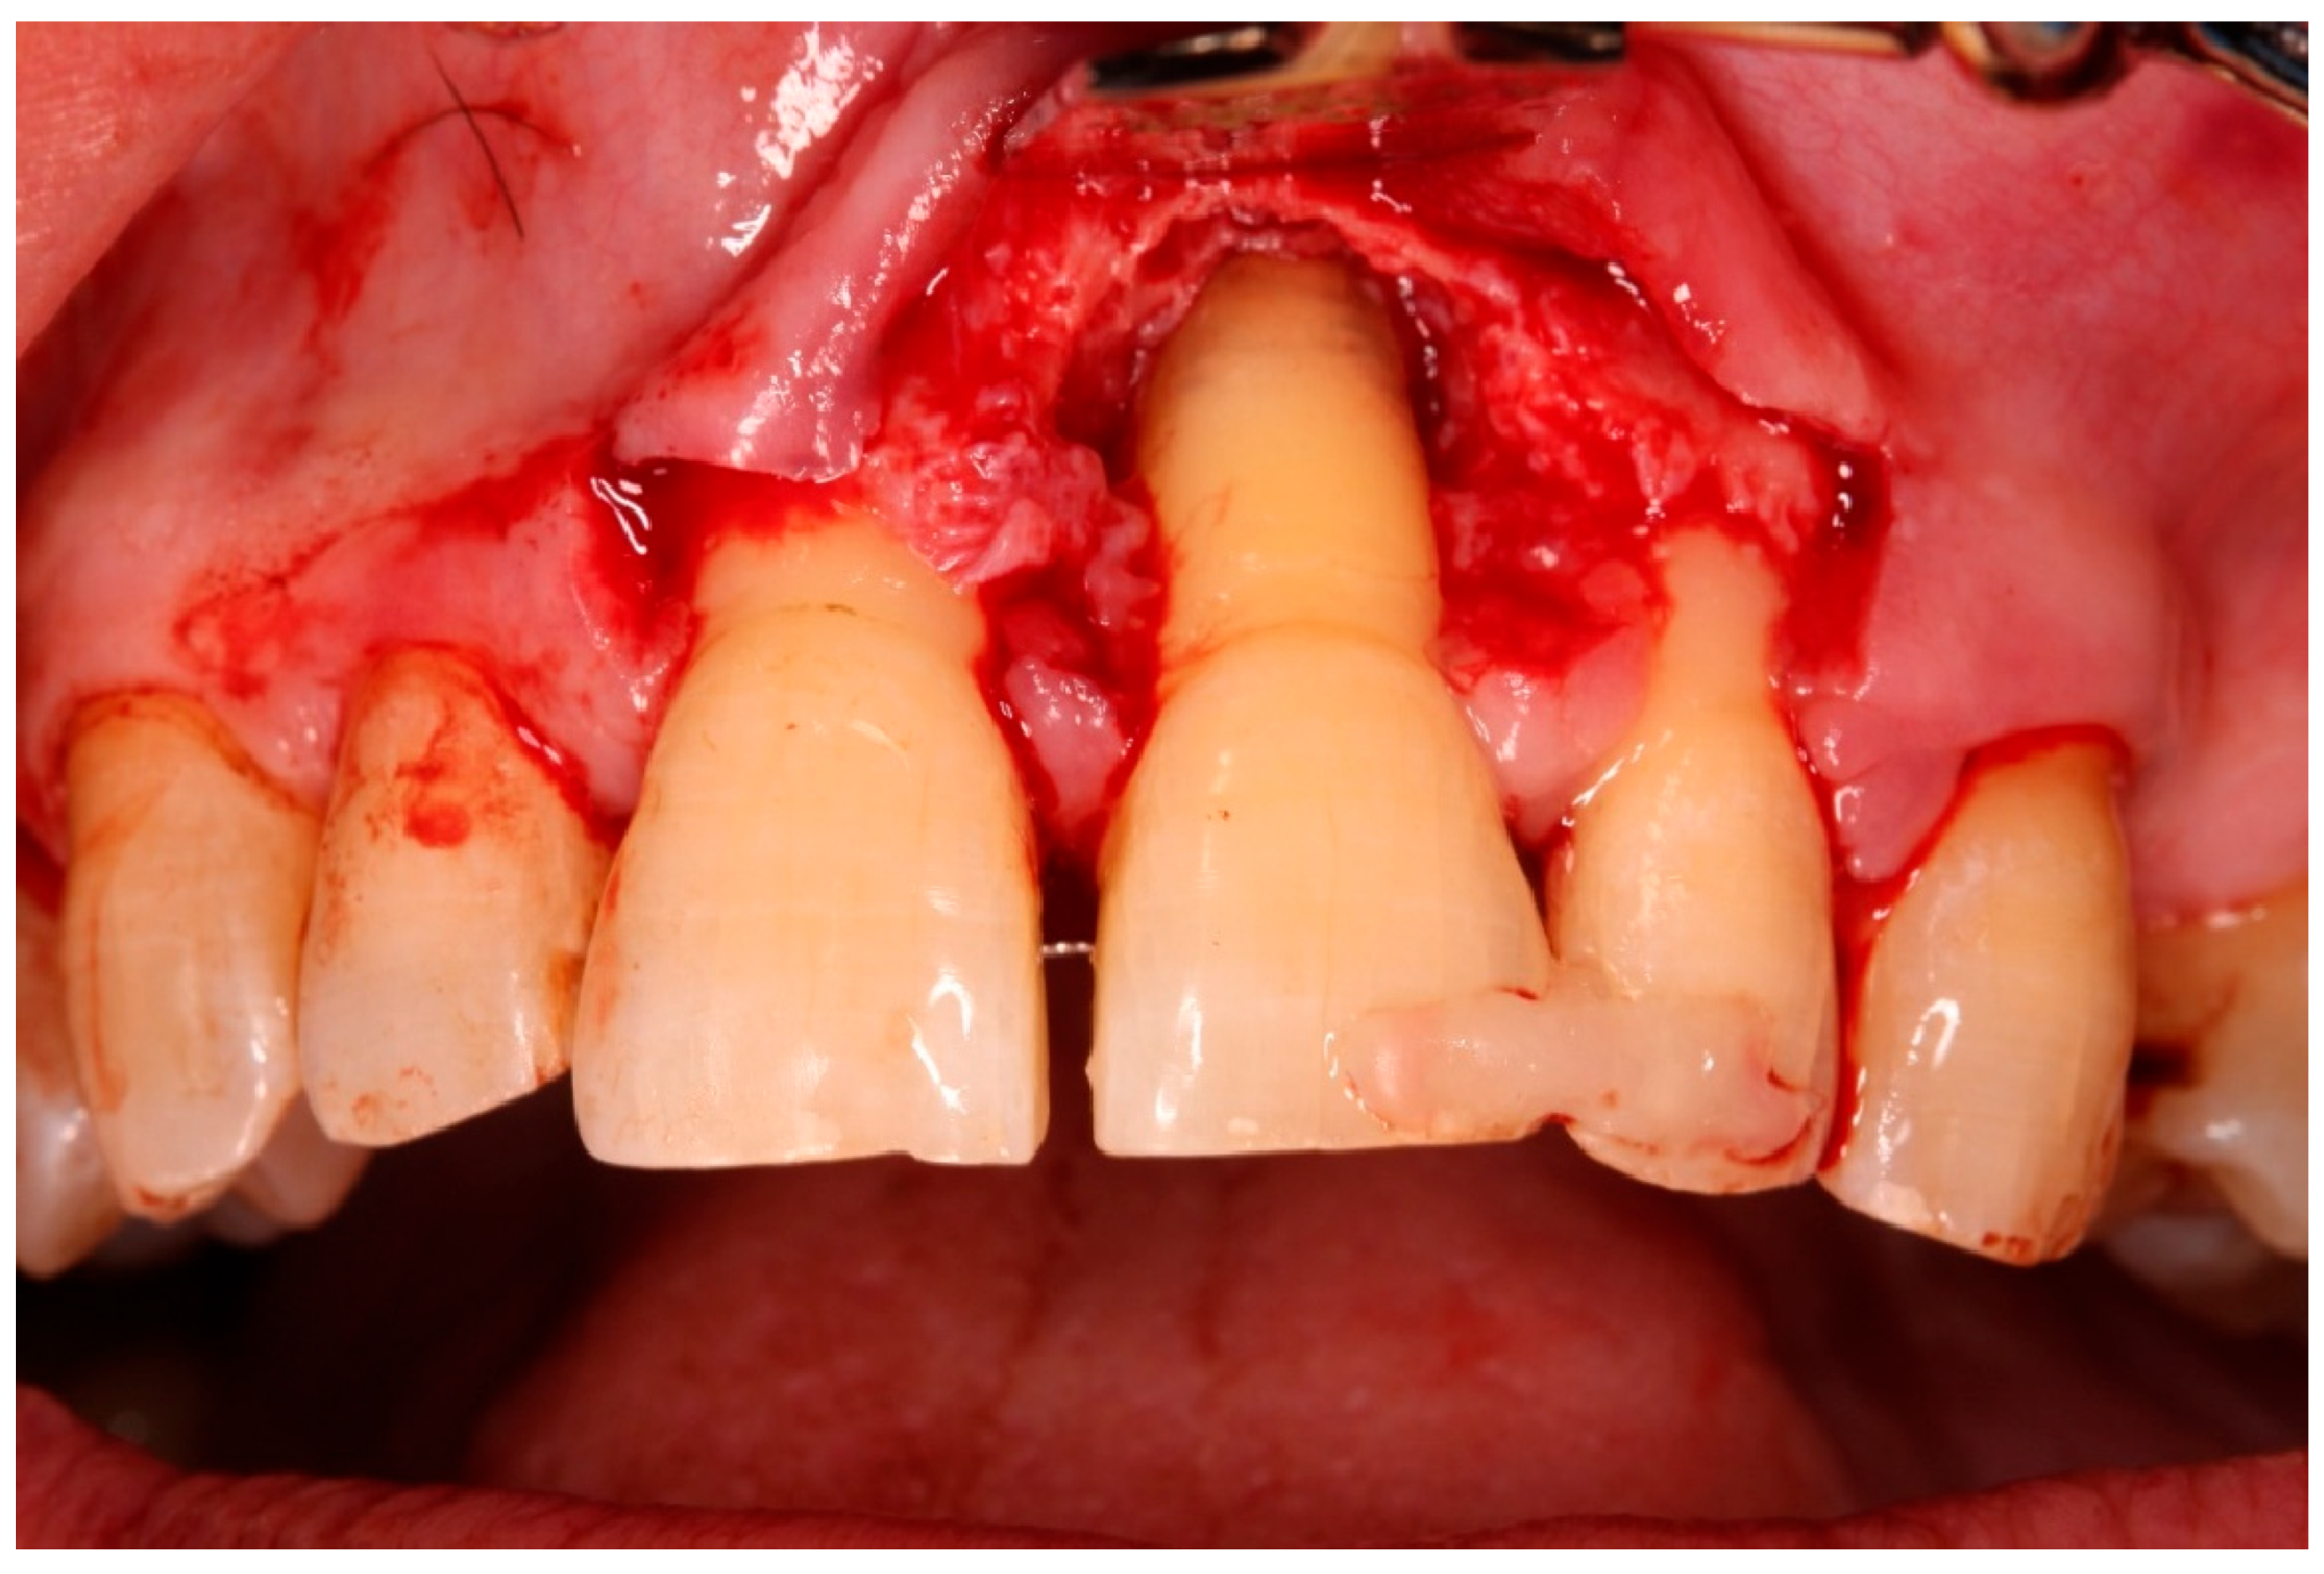

- Preparation of the recipient socket: After curettage of granulation tissue from the original socket, the CAD/CAM surgical guide was positioned. A guided osteotomy was performed using the implant-type drills from the C3D Cambados guided surgery kit, following the virtual plan. A biologic drilling protocol without irrigation was used to preserve autologous bone chips in the osteotomy walls. These chips were collected and later used as graft material. Drill sequence, diameters, and depth calibration followed the manufacturer’s recommendations and the digital plan, maintaining a stable trajectory and preserving palatal bone for primary stability.

- Guided tissue regeneration: A full-thickness flap was elevated to expose the defect morphology. Autologous bone chips collected during drilling were combined with xenograft particles (Bio-Oss®, Geistlich Pharma, Wolhusen, Switzerland) and enamel matrix derivative (Emdogain®, Straumann, Basel, Switzerland) and placed around the replanted root. A resorbable collagen membrane (Bio-Gide®, Geistlich Pharma, Wolhusen, Switzerland) was positioned to stabilize the grafted area and support space maintenance. The flap was repositioned and sutured to achieve primary closure.